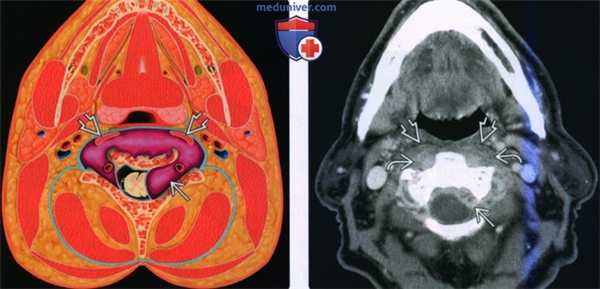

Схема, аксиальный срез на уровне ротоглотки. Показаны предпозвоночный и околопозвоночный отделы паравертебрального пространства, покрытые глубоким листком глубокой фасции шеи. Обратите внимание, что фасция делает изгиб в медиальном направлении, крепится к поперечным отросткам позвонков и подразделяет паравертебральное пространство на два отдела. Спереди от него расположены опасное и заглоточное пространства, сзади и с латеральной стороны-заднее шейное пространство.

(Слева) Схема аксиальной проекции на уровне ротоглотки. Показано условное новообразование паравертебрального пространства, которое смещает предпозвоночные мышцы и разрушает тело позвонка. Обратите внимание, что глубокий листок глубокой фасции шеи ограничивает распространение опухоли и «направляет» ее в эпидуральное пространство.

(Справа) КТ с КУ, аксиальный срез на этом же уровне. Флегмона-абсцесс в предпозвоночной части паравертебрального пространства. Отмечается накопление контраста. Слева виден эпидуральный абсцесс. Обратите внимание, что предпозвоночные мышцы смещены кпереди.